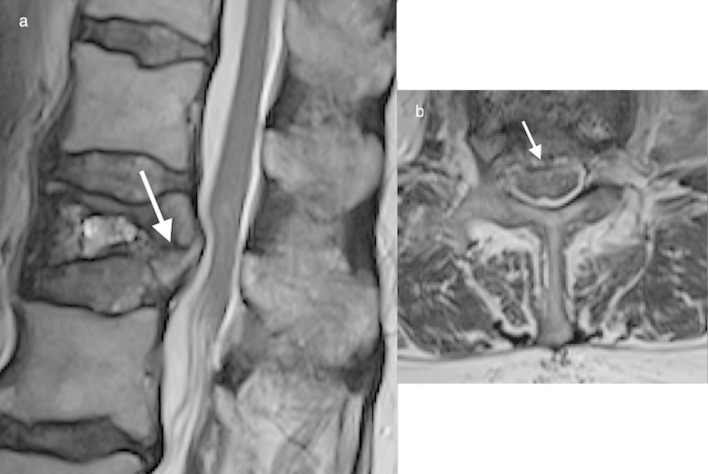

Due to the movement of CSF, SAH usually spreads longitudinally rather than becoming contained focally.4,10 A distinguishing feature of a SAH is the presence of fluid levels (Figure 8). SAH may layer within the distal thecal sac (Figure 9). As in subdural haemorrhage there is preservation of the epidural fat signal, and the normal dural demarcation is present.

Figure 8.

Sagittal T1 (a) and T2 (b) weighted images of the thoracolumbar spine, and axial T2 (c) weighted image of the lumbar spine depicting an extensive subarachnoid haematoma, fluid–fluid levels are a distinguishing feature of SAH. SAH usually spreads rather than becoming contained focally and may layer within the distal thecal sac. SAH,subarachnoid haemorrhage.

Figure 9.

T2sagittal (a) and axial (b, c) demonstrates subdural and SAH in the lumbar spine post-trauma; a 3 mm subdural haematoma is seen anteriorly (white arrows) and fluid–fluid levels indicate SAH settled posteriorly (black arrows). SAH,subarachnoid haemorrhage.